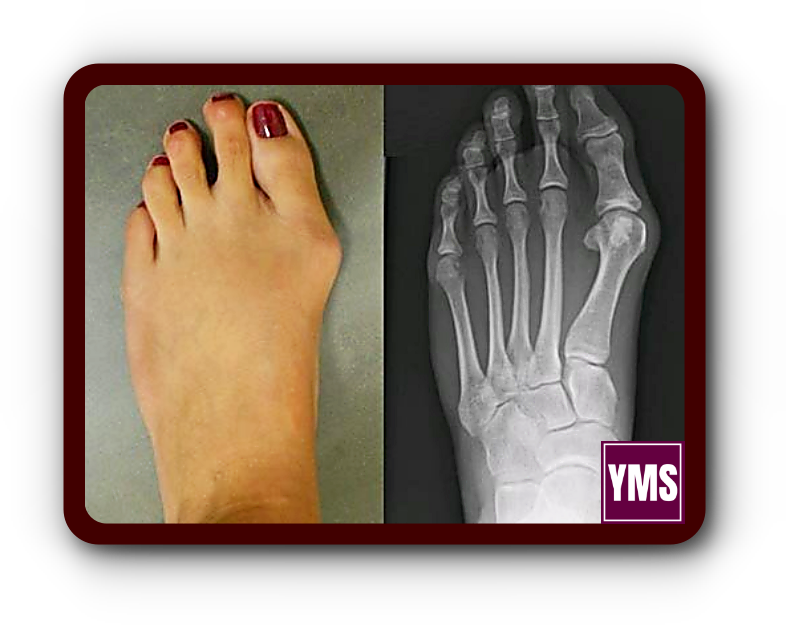

무지외반증은 엄지발가락이 바깥쪽으로 크게 휘어져 발생하는 발의 변형을 말합니다. 많은 사람들이 이 변형을 보고 무지외반증 통증이 심할 것으로 예상하지만, 실제로는 수술 후 대다수 환자가 "생각했던 것보다 통증이 적다"고 이야기합니다.

원위 갈매기형 절골술은 엄지발가락과 그 옆 발가락 사이가 벌어진 것을 교정하는 수술입니다. 이 방법은 엄지발가락의 뼈를 V자 모양으로 절단한 뒤, 바깥쪽으로 옮기고 고정시킵니다.